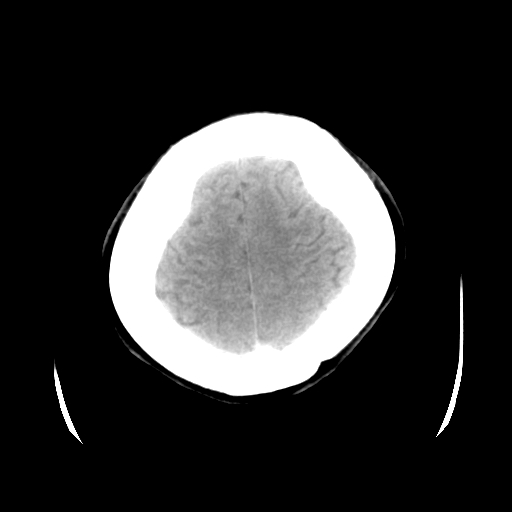

以下是引用cgf在2010-1-3 17:53:00的发言:[br]此病例多考虑:透明隔发育异常 透明隔囊肿可能性大;右侧基底节区(尾状核头)小片状低密度影考虑陈旧性腔梗[br][br]透明隔发育异常:包括透明隔间腔(第五脑室)、韦氏腔(第六脑室)、透明隔囊肿、透明隔缺如;前两者属于正常变异,后两者属于发育畸形;[br]透明隔间腔向下扩张形成韦氏腔;[br]有时透明隔间腔与透明隔囊肿很难鉴别;透明隔间腔间距一般不超过0.5cm,间距大于0.5cm时应考虑透明隔囊肿;[br]透明隔缺如为两侧脑室间隔缺如、融合成单脑室畸形,可伴有智力发育异常;[br][br]

以下是引用liaoqiang在2010-1-3 16:04:00的发言:[br]考虑侧脑室脉络丛囊肿?不除外变异的威氏腔。

以下是引用江广1996在2010-1-3 20:17:00的发言:[br]考虑变异的威氏腔。不除外侧脑室脉络丛囊肿.[br]透明隔囊肿大多数偏前,在侧脑室前角之间。